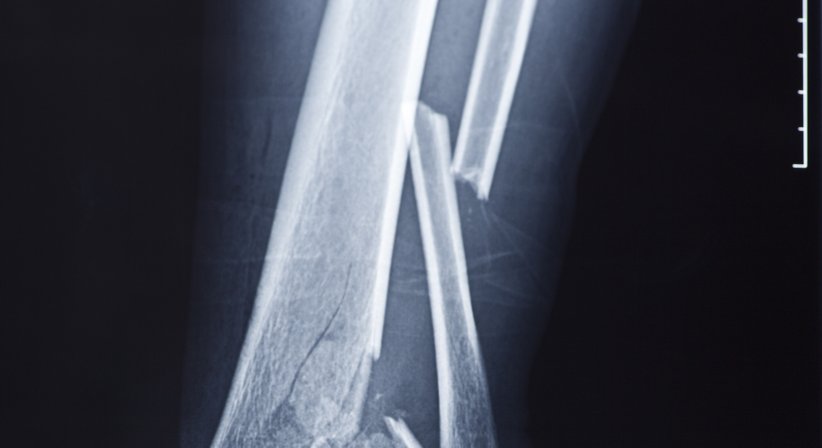

Unterarmbruch

Zu einem Unterarmbruch kommt es in der Regel durch einen Sturz auf die Hand oder den Unterarm. Entweder ist die Elle oder die Speiche gebrochen. Manchmal sind auch beide Knochen von der Fraktur betroffen.